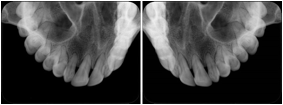

Intra-oral Full Mouth Series Structured Display

Figure OO-1. Intra-oral Full Mouth Series Structured Display